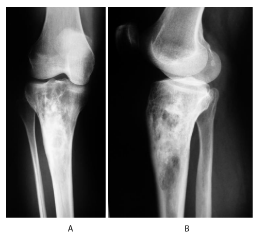

A 33 year - old female patient presented for right leg pain of a five week duration, exacerbated by weight bearing without disappearing at rest or at night. She estimates the pain as 6 over 10, relieved with non-steroidal anti - inflammatory agents. She is previously healthy without any history of trauma. There is mild edema, no redness, and mild increase of the pain upon palpation. There are no neurovascular abnormalities. Examination of the back, hip, and knee is normal. X-ray showed a large hypolucent spherical lesion in the proximal third of the tibia (Figure 1). MRI on T1 showed the lesion to be hypointense, and on T2 to be hyperintense (Figure 2,3). The lesion showed to be osteolytic, extending anteroposteriorly through the cortex at some levels, but it did not reach the articular surface, nor the surrounding soft tissues. Decision was taken to biopsy it. The pathology report showed lamellated cysts and scattered scoleces. Albendazole 400 mg was given orally twice per day for 2 months. Extensive curettage was done through excision of bone layers with a burr, then phenolization and grafting of cancellous bone chips inside the cavity. The patient was free clinically and radiologically of the disease for two years, then in the third year, multilocular cysts reappeared on x-ray (Figure 4), with possible extension to the articular surface. A decision of total knee arthroplasty was taken after wide resection of the diseased segment (Figure 5). Negative margins were obtained. The patient post operatively was rehabilitated; pain subsided with no radiological signs of recurrence. She was given albendazole 400 mg orally twice per day for 3 months.

Figure 2: On the left: T1 coronal cuts showing hypointense proximal tibia lesion not reaching the articular surface, nor invading the surrounding soft tissues. On the right: T2 coronal cuts showing hyperintense lesion.